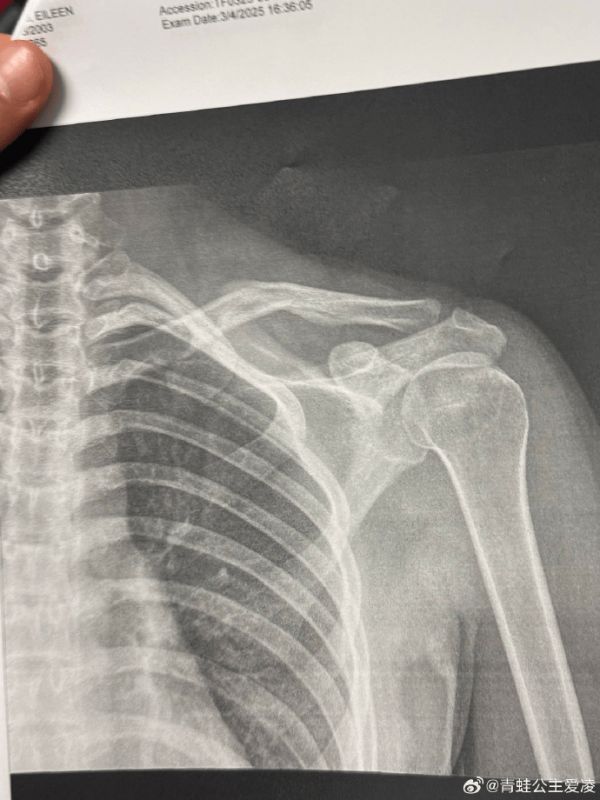

在1月底进行的阿斯本极限运动会上,谷爱凌在比赛中摔倒受伤,并退出了随后的比赛。她曾表示,摔倒造成了严重的挫伤,自己在受伤后走不了路。

据悉,谷爱凌两个脚踝在训练中都受伤了,身体也出现了咳嗽和发烧的情况,谷爱凌表示一直在坚持,身体已经到达了极限。

2月4日,谷爱凌发文称,自己将退出盼望已久的亚冬会,并将积极配合医生康复治疗,争取尽快回到赛场。